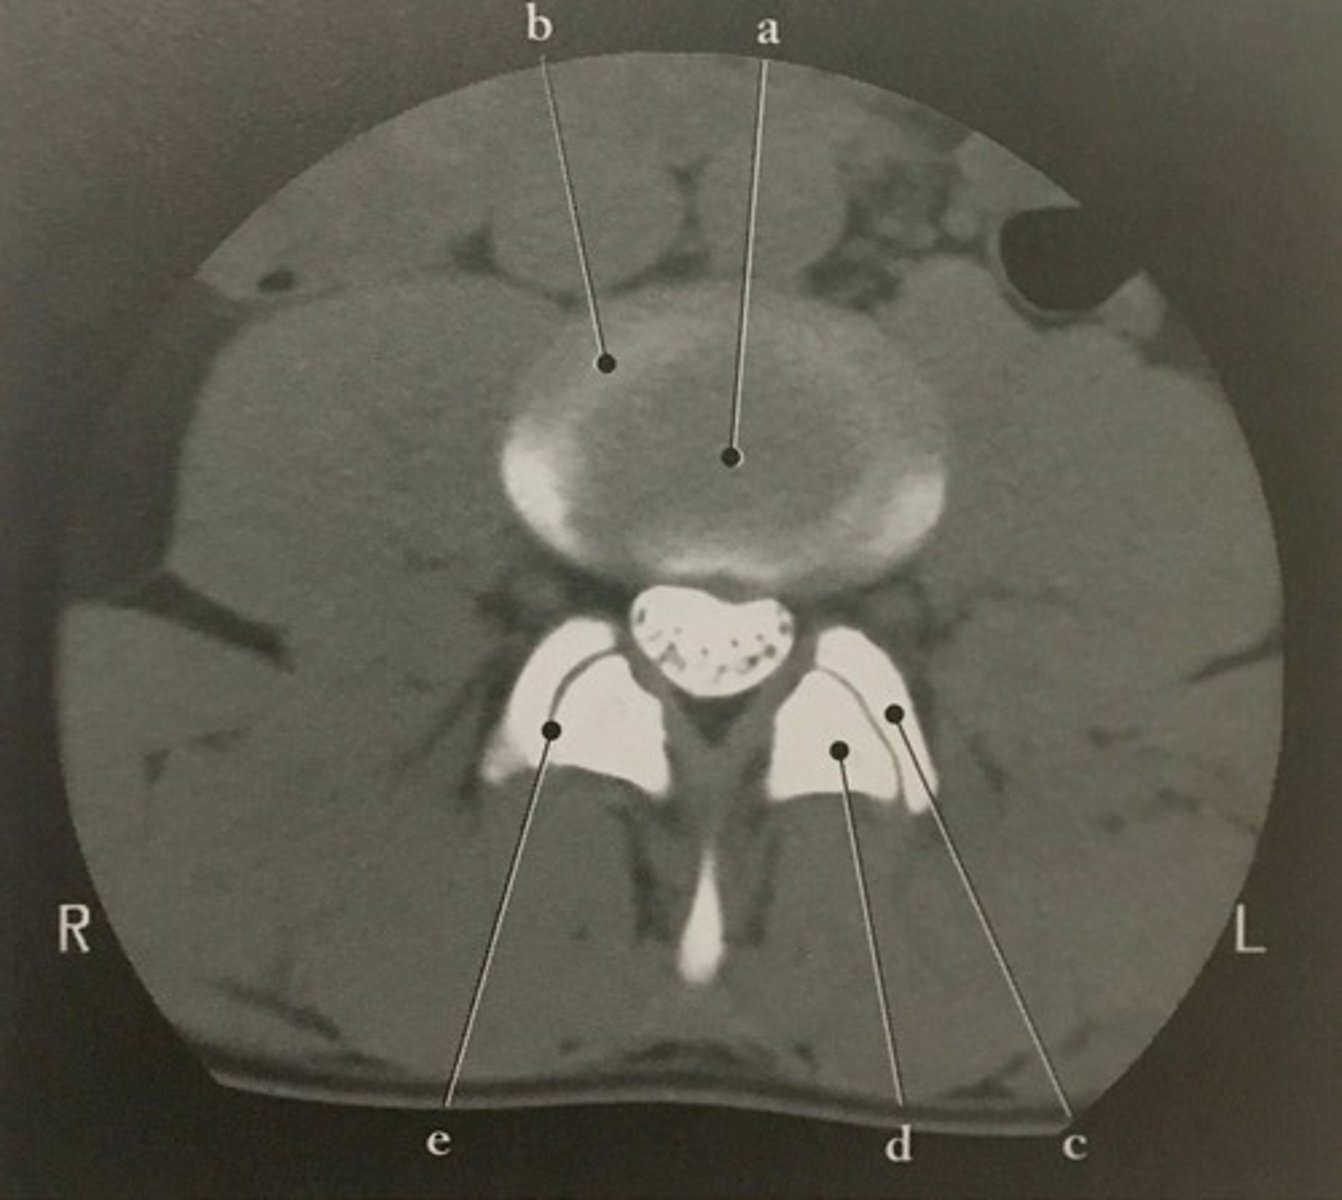

Superior articular process

Identify structure C on this axial CT slice of the lumbar spine with intervertebral disk.

<p>Identify structure C on this axial CT slice of the lumbar spine with intervertebral disk.</p>

91

New cards

Inferior articular process

Identify structure D on this axial CT slice of the lumbar spine with intervertebral disk.

<p>Identify structure D on this axial CT slice of the lumbar spine with intervertebral disk.</p>